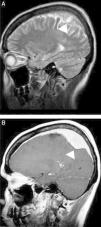

Peculiar presentations of primary central nervous system lymphomasLeptomeningeal infiltration in the course of lymphoma, particularly in systemic disease, is not rare. However, this imaging appearance is nonspecific and may alternatively occur after CNS invasion by infection or in several other primary and systemic malignancies (meningeal carcinomatosis). Associated periventricular masses, mainly with subependymal infiltration, may corroborate a diagnosis of CNS lymphoma in a differential diagnosis.1 Dural-based lymphoma, particularly the mucosa-associated lymphoid tissue (MALT) subtype, mimics meningiomas; therefore, a careful interpretation of imaging findings in the clinical scenario is recommended. Few reports have described the typical presentation of intracranial MALT lymphoma-mimicking globular meningiomas (Figure 4).1,26–28

Mucosa-associated lymphoid tissue (MALT) lymphoma mimicking meningioma. A sagittal T2-weighted image (A) shows a solid extra-axial lesion that infiltrated the dura mater in the parietal region (arrowheads). A comparative image on a T1-weighted sequence after intravenous gadolinium administration (B) confirmed homogeneous contrast enhancement that was associated with an extensive dura tail, which mimicked the appearance of a meningioma (arrowhead).

The diagnostic possibility of a cranial vault lymphoma is greater when the lesion involves the scalp, the skull bone, and the pachymeninges, mainly in the absence of bone erosion (Figure 5). However, this pattern of lesion is not specific to PCNSL because it has been observed in systemic lymphoma and in many mimic lesions, including metastatic infiltration from prostate carcinoma and breast cancer, osteomyelitis, meningioma, plasma cell tumors, and histiocytosis.29

A cranial vault lymphoma. An axial T2-weighted image (A) shows a small multicompartmental lesion in the occipitoparietal region (arrow). Axial diffusion-weighted imaging (B) shows restricted water molecule diffusion in the solid portions of the lesion. A comparative T1 image after intravenous gadolinium administration (C) shows an enhanced lesion that involves the scalp, the skull bone, and the pachymeninges and extends to the leptomeninges (arrowhead). A non-enhanced computed tomography scan (D) confirmed the absence of bone erosion.